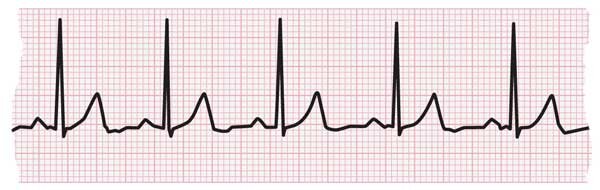

- الکتروکاردیوگرام (ECG یا EKG): الکتروکاردیوگرام فعالیت الکتریکی در قلب شما را ثبت می کند و به پزشک کمک می کند تا علائمی را جستجو کند که طبیعی به نظر نمی رسند. ممکن است مجبور شوید از هولتر مانیتور استفاده کنید، یک دستگاه قابل حمل که سیگنال های ECG شما را در مدت 24 ساعت ضبط می کند.

نوار ECG که ضربان قلب طبیعی را نشان می دهد

نوار ECG نشان دهنده تاکی کاردی است